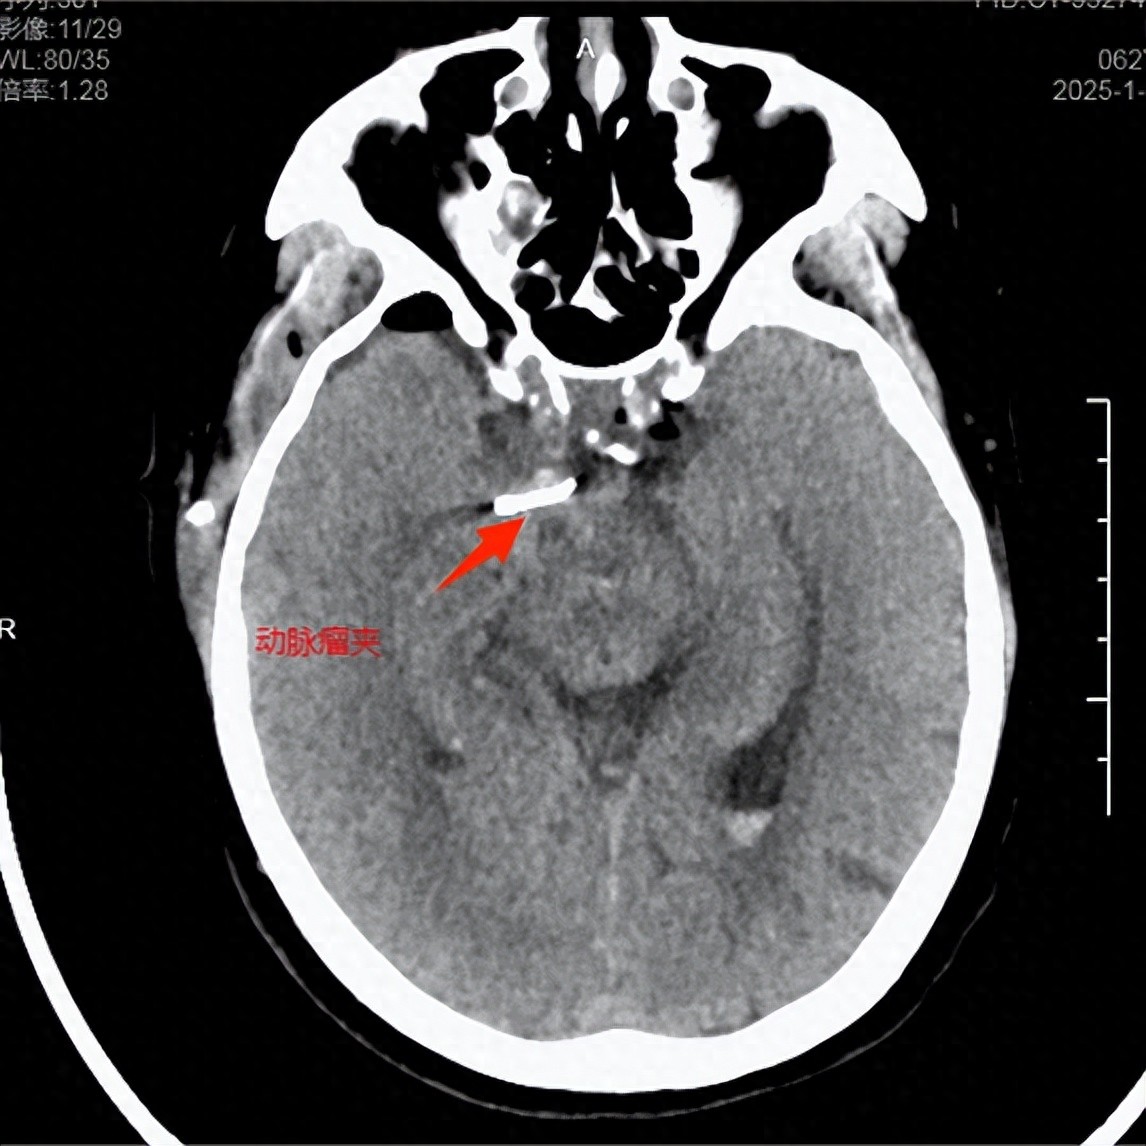

术前ct术后ct动脉瘤已夹闭

cta显示动脉瘤夹闭完全,载瘤动脉保留完好,无明显的血管痉挛.